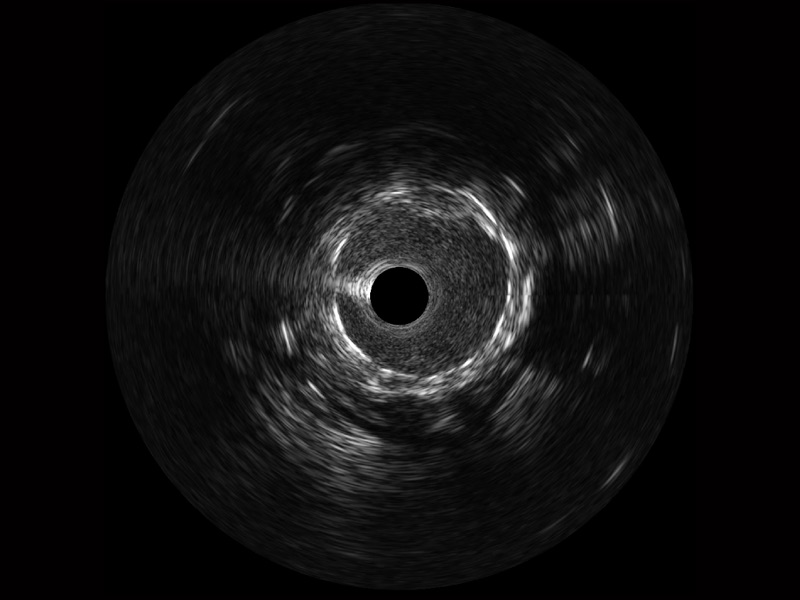

• 美狮贵宾会官网宽频IVUS图像

• 传统IVUS图像

对比传统IVUS导管成像,美狮贵宾会官网宽频IVUS图像的近场支架梁显影更细腻,远场中膜外血管仍清晰可辨,兼顾远中近,兼顾分辨力与穿透深度